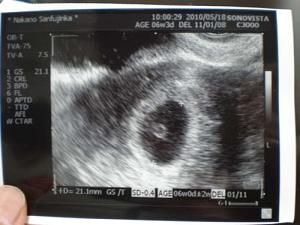

まだ心拍が完全には確認できず、次の診察まであと1週間以上あるので不安はあります。たまに茶おりが出たり、コレといったつわりなどの初期症状もありません。でも妊娠がわかってから仕事も辞め、安静に過ごすようにしています。無事に赤ちゃんが育っていることを願う日々です。